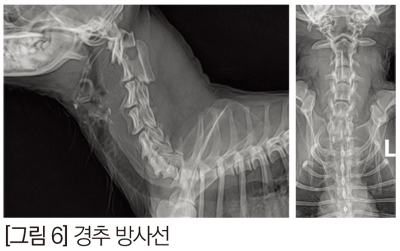

병원에 2.2 kg 11년생 Maltese가 사직 강직과 기립 불능으로 내원하였다. 내원 당시 모든 다리에 UMN 증상이 있고, 심부 통증은 존재했다. 내원하기 1년 전에 디스크 관련 약물을 처방 받아서 먹은 경력이 있었고, 일주일 전부터 활력의 저하가 보이면서 내원 당일 아침에는 기립이 불가능해졌고, 최근 dysuria 병력이 있었다. 혈액 검사에서는 특이 사항은 없었고, 방사선 검사에서 경추 5번에서 7번까지 좁은 disc space를 보여 경추 디스크의 가능성을 보였다. [그림 5]

경추 디스크의 압박 정도와 척수 실질의 평가를 위해 추가 MRI 검사를 실시하였고, MRI 판독에서 경추 5번과 6번, 그리고 6번과 7번 사이 척추 공간의 감소와 T2W1과 T1W1 영상에서 디스크의 탈출을 확인했는데, 5번과 6번 사이 compression 정도는 39%, 6 번과 7번 사이 compression 은 17% 정도로 5번과 6 번 사이가 주요 병변임을 확인했다. [그림 6]